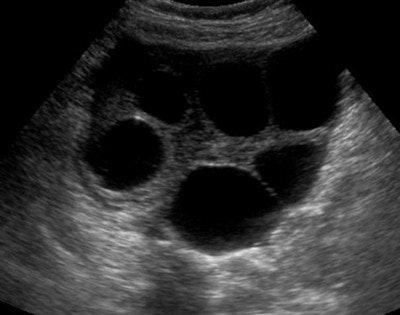

| Pyosalpinx: Patient presented with lower abdominal pain and increased inflammatory markers. Transvaginal ultrasound demonstrated dilated serpentine structures with internal echogenic debris representing infective pus within the fallopian tubes. |